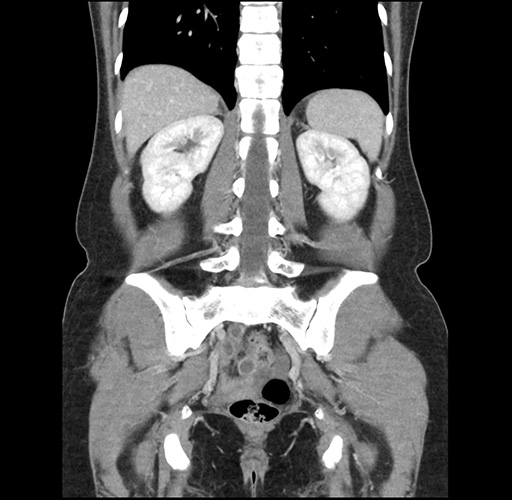

Imaging Analysis

Look through the patient's CT scan to identify any areas of concern for the necessary procedure.

Based on your CT findings, which issue(s) would give reason for "planned slowing down moment(s)" in this case?